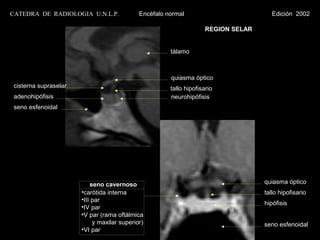

CATEDRA DE RADIOLOGIA U.N.L.P.              Encéfalo normal                           Edición 2002

REGION SELAR

tálamo

quiasma óptico

cisterna supraselar                                   tallo hipofisario

adenohipófisis                                       neurohipófisis

seno esfenoidal

seno cavernoso                                           quiasma óptico

•carótida interna                                            tallo hipofisario

•III par

hipófisis

•IV par

•V par (rama oftálmica

y maxilar superior)                                     seno esfenoidal

•VI par